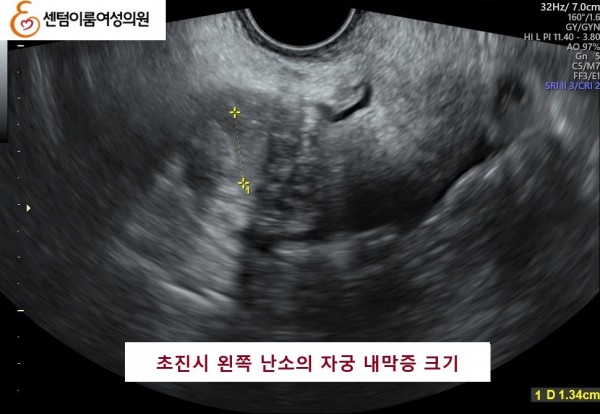

2025.6.28 본원에 내원시 양측 자궁 내막종이오른쪽 4.5cm , 왼쪽 1.3cm 정도 였습니다.

난소의 자궁 내막종은 난소기능 저하를 유발시켜 난자의 갯수를 작게 만듭니다.

본 원에서 수술없이 알콜경화술 3개월 후 양측 다 사라진 사례입니다.